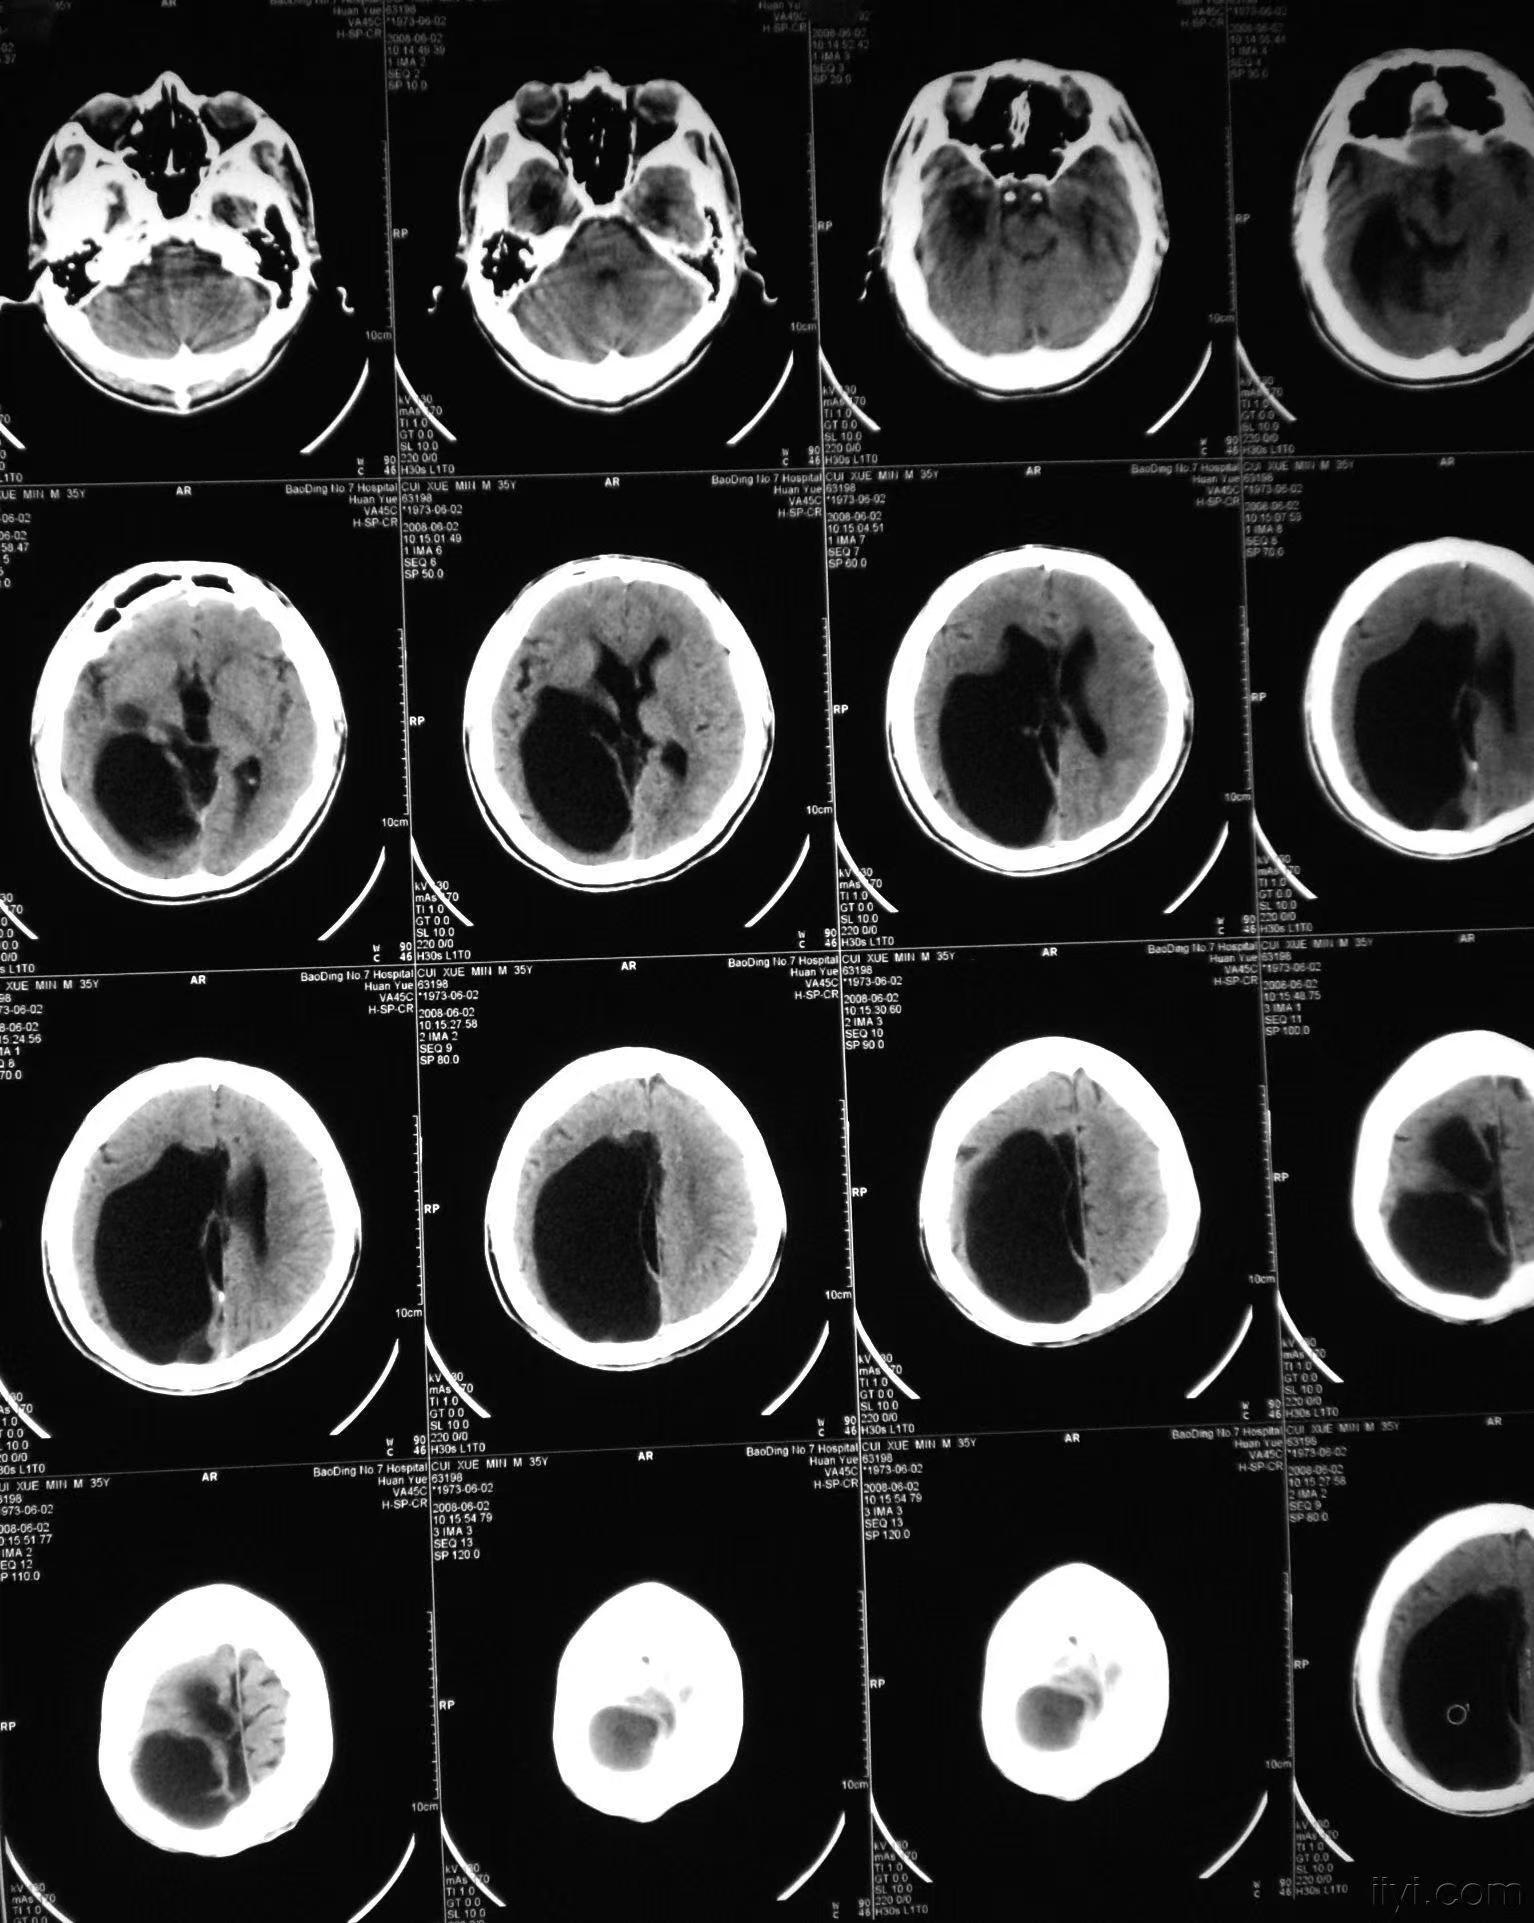

(五)CT扫描 能直观地显示脑穿通畸形的存在及类型,对了解囊肿的大小、部位、形态、数目及治疗方案选择、预后估计、鉴别诊断等均有重要意义。CT表现脑内囊肿性病变,CT值与脑脊液相似,病灶部位低密度影,与脑室相通。其他表现有脑积水、脑皮层萎缩等。强化扫描不增强。